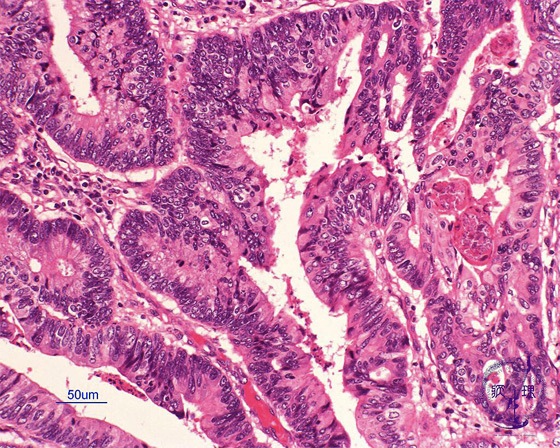

Microscopic view (H&E stain, high power): Well differentiated tubular adenocarcinoma with unambiguous tubule formation (tub1).